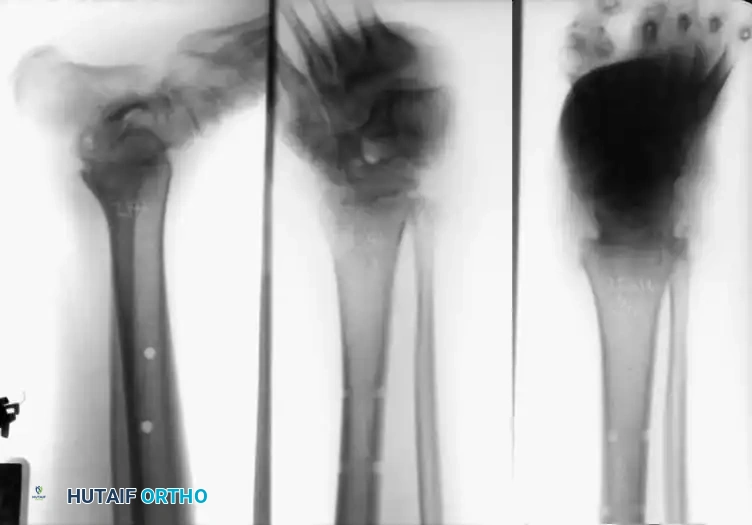

Ankle Arthrodesis

Arthrodesis of the ankle is performed with significantly greater frequency than that of the hip or knee. The most common indication is end-stage posttraumatic arthritis, which accounts for over 70% of cases.

Other primary indications include rheumatoid arthritis, chronic osteomyelitis, neuromuscular instability, and the salvage of a failed total ankle arthroplasty (TAA). Recently, ankle arthrodesis has seen increased utilization in patients with severe, nonbraceable neuropathic (Charcot) arthropathy. However, surgeons must be acutely aware that complication rates—specifically deep infection and nonunion—are exponentially higher in the neuropathic population. Advanced techniques, such as the use of adolescent condylar blade plates, large-diameter cannulated AO screws, and antibiotic-impregnated allograft mixtures, have been developed to mitigate these risks.

In cases of severe osteopenia or when extending the fusion to the subtalar joint (Tibiotalocalcaneal Arthrodesis), retrograde intramedullary nailing provides a load-sharing construct with superior bending stiffness.